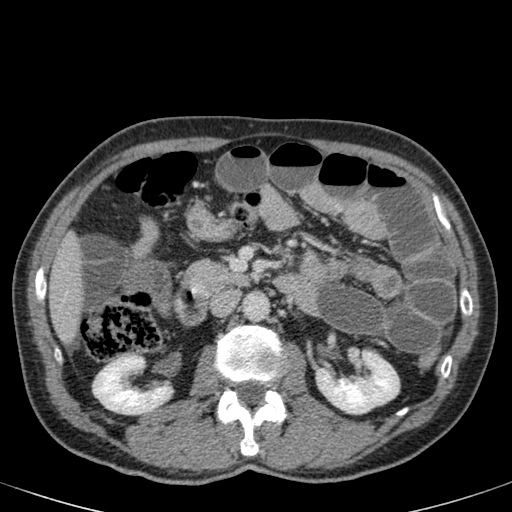

Đây là một bệnh nhân bị tắc ruột non.

Cuộn qua các hình ảnh.

Bạn có thể tìm thấy quai kín và nguyên nhân gây ra nó không?

Khi tiếp nhận bệnh nhân tại phòng cấp cứu với biểu hiện nghi ngờ tắc ruột non (SBO), điều quan trọng nhất chúng ta cần làm, ngoài việc chẩn đoán xác định, là xác định sự hiện diện hay vắng mặt của tình trạng thắt nghẹt.

CT là phương pháp chẩn đoán hình ảnh được lựa chọn trong đánh giá bệnh nhân nghi ngờ tắc ruột non.

Hình ảnh CT của tắc ruột non dạng quai kín phụ thuộc vào hai yếu tố:

- chiều dài đoạn ruột tạo thành quai kín

- hướng của quai ruột so với mặt phẳng tạo ảnh

Nếu quai kín ngắn và nằm trong mặt phẳng tạo ảnh, chúng ta sẽ thấy quai ruột hình chữ U hoặc chữ C.

Một hình ảnh quan trọng khác của tắc ruột dạng quai kín là các quai ruột non giãn xếp theo hình nan hoa với các mạch máu mạc treo hội tụ về một điểm trung tâm.

Hình ảnh này hầu như luôn do xoắn ruột non gây ra.